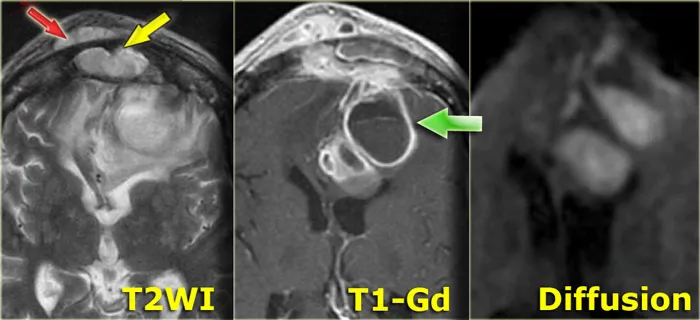

| CT/MRI | Lentiform, biconvex; no suture crossing | Crescentic; crosses sutures, interhemispheric | Ring-enhancing lesion; central necrosis, edema |

📌 Brain Abscess Stages (CLEMA): Cerebritis Early, Late Cerebritis, Early Capsule, Mature (Late) Capsule, Abscess.